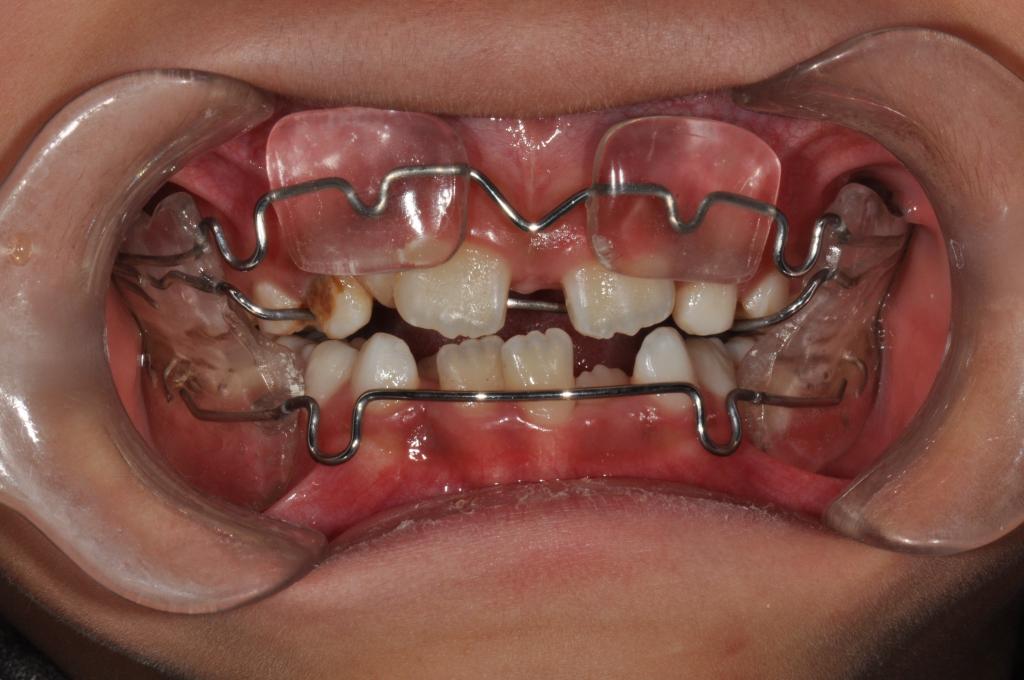

② 前方牵引矫治器

③ Frankel Ⅲ矫治器